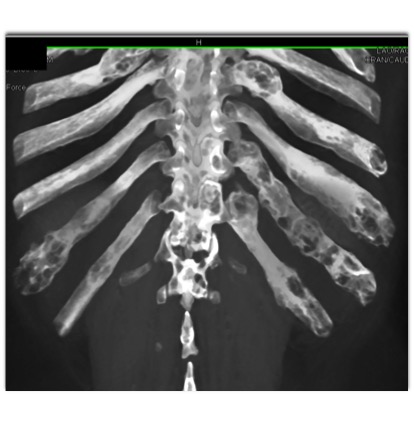

The best diagnosis in this case is?

multiple myeloma

fibrous dysplasia

metastatic renal cell carcinoma

Pagets Disease